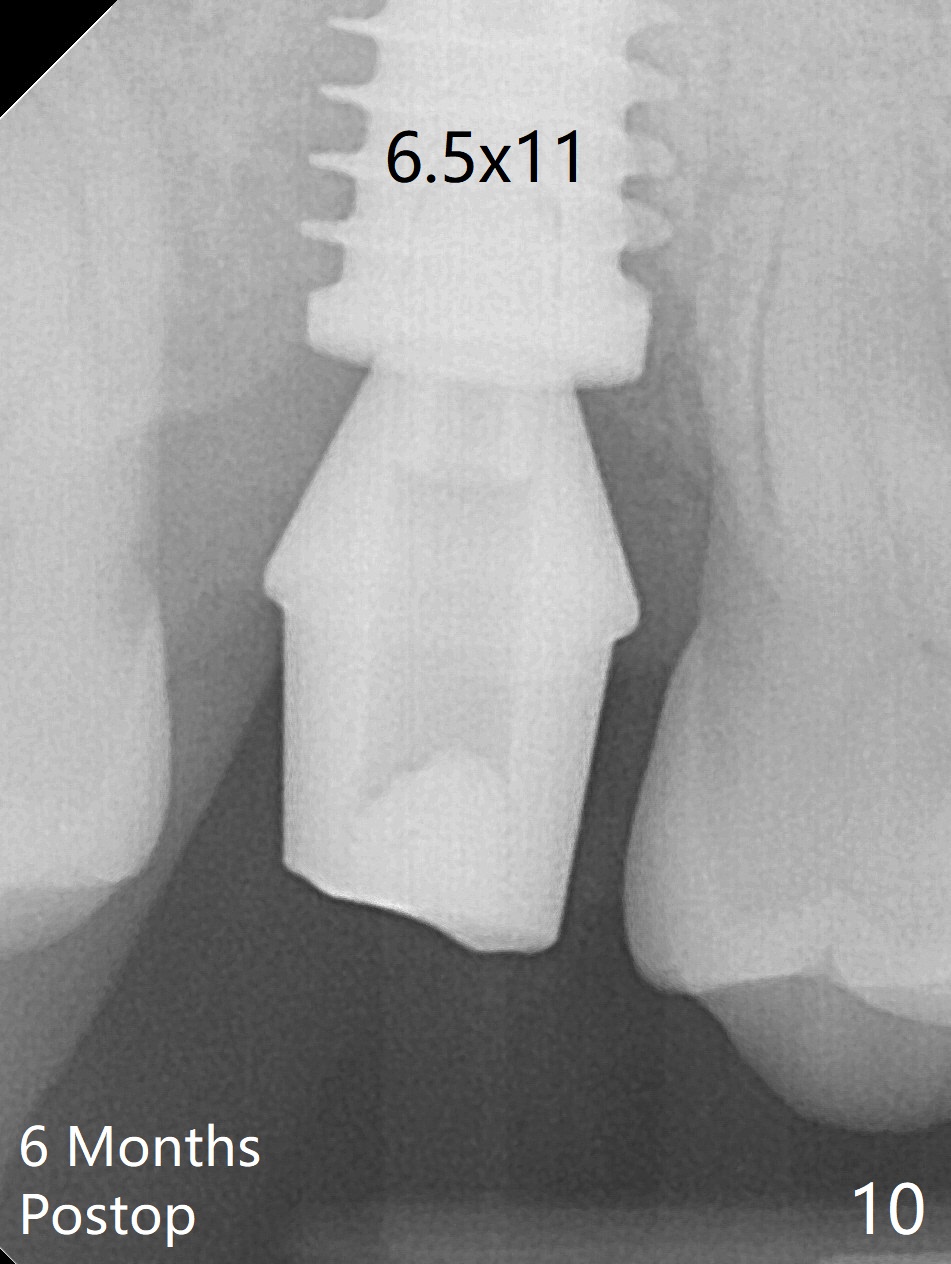

When the 59-year-old man returns for #24 implant placement, the tooth #2 is found to have crack (Fig.1,2 arrowheads), associated with buccal and palatal fistulae (*) and loss of amalgam (Fig.4 *). Abundant granulation tissue is attached to the roots of the affected tooth (Fig.3), indicating severe bone loss. There is a plateau associated with the septum and buccal sockets, which is the site of osteotomy. Magic split and 3 and 3.8 mm Magic Expanders are used to initiate osteotomy. After use of 4.3 mm Magic Drill for about 3 mm, Osteogen plug and allograft are used for sinus lift, followed by insertion of a 4.5x11 mm dummy implant (Fig.5). When a 5.5x9 mm dummy implant is placed with stability, it appears to be seated cervical (Fig.6,7). When a 6x9 mm IBS implant (definitive) is placed with a 6.5x5.5(4) mm abutment, they are seated too deep for provisional (Fig.8). The implant/abutment are removed and replaced by a 6.5x11 mm one in a shallower position; after trimming the same abutment as mentioned above (Fig.9), an immediate provisional is fabricated to keep bone graft in place. Fabrication of Tap with soft tissue markers will reduce the chance of miscalculation and waste of implants. The coronal threads of the implant are covered with bone 6 months postop (Fig.10). One month later when a permanent crown tries in, the implant is found to be loose and tender. A healing abutment is placed. Six months later, the patient returns for crown retry-in. The tooth #1 seems to have shifted mesially (Fig.11 arrow). When the abutment is placed, the implant remains tender and loose. After implant removal with a wrench, there is no granulation tissue or bony defect, including the intact sinus floor (Fig.12 <). Since the tooth #1 has deep periodontal pockets and mobility, the tooth is extracted with abundant granulation tissue. After debridement, Osteogen plug is placed in the socket of #1, while Vanilla graft is placed at the site of #2 (Fig.13 *). Three weeks later, the socket of #2 heals with exposure of Osteogen plug (Fig.14 (B: buccal)).